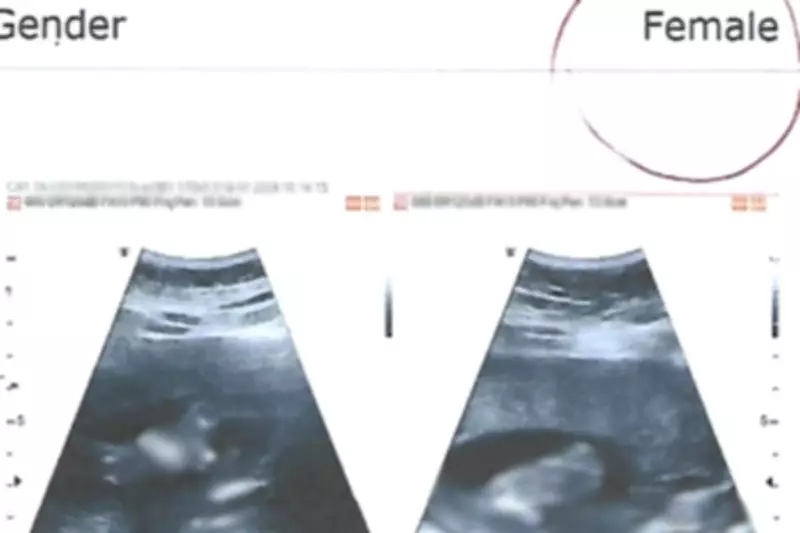

De acordo com os autos do processo, a família organizou um chá revelação e preparou um enxoval completo com itens tipicamente femininos após o exame realizado em janeiro de 2024, quando a gestante estava no segundo trimestre de gravidez. O resultado do ultrassom, feito no Centro Médico Clinimagem, apontou que o bebê era do sexo feminino, informação que foi repassada apenas para a comadre da gestante, pois os pais planejavam descobrir o sexo durante a festa.

O juiz Sergio Castresi de Souza Castro, da 4ª Vara de Cubatão, destacou em sua sentença que a perita foi contundente ao afirmar que, no segundo trimestre de gestação, a precisão do exame de ultrassom atinge 99%, e que a identificação do sexo feminino não pode ser presumida apenas pela ausência de pênis na imagem.

Em sua manifestação, a defesa do médico argumentou que o exame realizado foi uma ultrassonografia morfológica de caráter diagnóstico, cuja finalidade principal é a avaliação detalhada do desenvolvimento fetal. A identificação do sexo fetal, embora possível nessa fase gestacional, pode sofrer limitações técnicas decorrentes de fatores como posição do feto, condições maternas e qualidade de imagem no momento do exame.